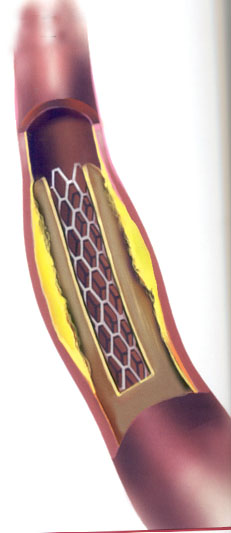

Ðñïò ôïýôï ôïðïèåôïýíôáé åíôüò ôçò äéáíïé÷èåßóçò áñôçñßáò äéêôõùôÜ ìåôÜëëéíá ðëÝãìáôá - åíäáñôçñéáêïß íÜñèçêåò (ÅÍ) (stents), ïé ïðïßïé , óáí åóùôåñéêü ðëÝãìá , óõãêñáôïýí áíïéêôü ôïí áõëü.

EíäïáõëéêÝò ðñïèÝóåéò ( stents)

Ç åíäïáõëéêÞ ðñüèåóç åßíáé ðñïóöÜôïõ åðéíïÞóåùò êáé ó÷åäéáóìïý ãéá íá êñáôÜíå ôïí áõëü ôïõ áããåßïõ áíïéêôü ðïõ ðñïçãïõìÝíùò äçìéïõñãÞèçêå áðüöñáîç Þ óôÝíùóç. Áêïëïõèåß ôçí áããåéïðëáóôéêÞ ìå ìðáëüíé, ïé áñôçñßåò ìåñéêÝò öïñÝò ìåôÜ áðü êÜèå áããåéïðëáóôéêÞ îáíáóôåíåýïõí ìå áðïôÝëåóìá íá Ý÷ïõìå ôá ßäéá óõìðôþìáôá üðùò ðñéí ôçí åðÝìâáóç. Ó áõôÞ ôçí ðåñßðôùóç îáíáãßíåôáé ç áããåéïðëáóôéêÞ ìå ìðáëüíé êáé ôïðïèåôåßôáé ç åíäïáõëéêÞ ðñüèåóç Þ åÜí äåí åßíáé äõíáôüí ãßíåôáé ðëÝïí ç êëáóéêÞ áããåéï÷åéñïõñãéêÞ åðÝìâáóç ìå BY-Pass äçë. ÷åéñïõñãéêÞ áðïêáôÜóôáóç êáé ðáñÜêáìøç ôçò âëÜâçò.

Ôá stents Þ åíäïáõëéêÝò ðñïèÝóåéò ôïðïèåôïýíôáé ìïíßìùò äçë. äåí áöáéñïýíôáé ìåôÜ , ôïðïèåôïýíôáé óôéò óôåöáíéáßåò áñôçñßåò óôá ðåñéöåñéêÜ áããåßá äçë. íåöñéêÝò, ëáãüíéåò , ìçñéáßåò, éãíõáêÝò , õðïêëåßäéåò , âñá÷éüíéåò êëð. êáèþò åðßóçò êáé óôá öëåâéêÜ ìïó÷åýìáôá BY-Pass .

Åßíáé Ýíá ìåôáëëéêü äéêôõùôü ðëÝãìá óå ó÷Þìá êõëßíäñïõ ôïðïèåôçìÝíï óå êáôÜëëçëï êáèåôÞñá ìðáëüíé êáé áöïý ôïðïèåôçèåß óôï óçìåßï ðïõ èÝëïõìå, íá äéáíïßîåé óôçí áñôçñßá, ôï ìðáëüíé öïõóêþíåé êáé åäþ ç åíäïáõëéêÞ ðñüèåóç stent áíïßãåé êáé åðéêïëëÜôáé óôá ôïé÷þìáôá ôïõ áããåßïõ êñáôüíôáò ôï áíïéêôü. Ï êáèåôÞñáò ìåôÜ áöáéñåßôáé êáé ôï áßìá ðëÝïí ðåñíÜ ÷ùñßò êáíÝíá åìðüäéï . Ôï stent Þ (åíäïáõëéêÞ ðñüèåóç) ìÝíåé ìüíéìá óôçí áñôçñßá åìðïäßæïíôáò ôçí íá îáíáêëåßóåé.

Ïé ÅÍ ÷áñáêôçñßæïíôáé áðü ôï ìç÷áíéóìü ôçò äéáôÜóåùò ôïõò äéáêñéíüìåíïé óå áõôïäéáôåéíüìåíïõò, èåñìïäéáôåéíüìåíïõò Þ äéáôåéíüìåíïõò ìå ìðáëüíé, Þ ðáñïõóéÜæïõí Üëëá ÷áñáêôçñéóôéêÜ âÜóåé ôùí ïðïßùí êáëïýíôáé áðïññïöÞóéìïé, ç êáëõììÝíïé.

ÂáóéêÜ ç åöáñìïãÞ ôïõò óôçí êëéíéêÞ ðñÜîç áðïóêïðåß óôç äéáôÞñçóç áíïéêôïý áããåéáêïý áõëïý, êõñßùò ôïõ áñôçñéáêïý , üðïõ óõíÞèùò åéóÜãïíôáé ðñïò åìðüäéóç ôçò áñôçñéáêÞò óõóðÜóåùò ç óôåíþóåùò .